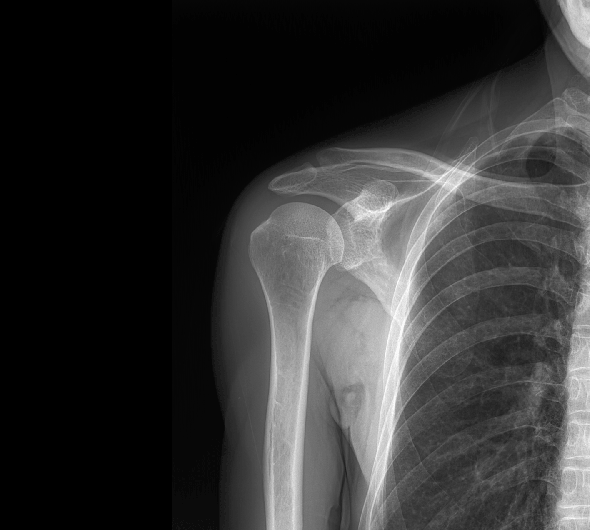

临床图像